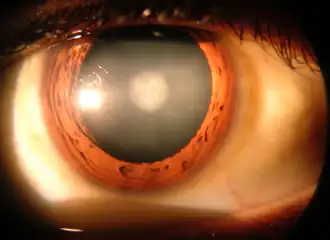

| Magnified view of a cataract seen on examination with a slit lamp | |

A cataract is a cloudy area in the lens of the eye that leads to a decrease in vision of the eye.[1][7] Cataracts often develop slowly and can affect one or both eyes.[1] Symptoms may include faded colours, blurry or double vision, halos around light, trouble with bright lights, and difficulty seeing at night.[1] This may result in trouble driving, reading, or recognizing faces.[8] Poor vision caused by cataracts may also result in an increased risk of falling and depression.[2] In 2020, Cataracts cause 39.6% of all cases of blindness and 28.3% of visual impairment worldwide. Cataract remains the single most common cause of global blindness.[3]

Cataracts are most commonly due to aging but may also occur due to trauma or radiation exposure, be present from birth, or occur following eye surgery for other problems.[1][4] Risk factors include diabetes, longstanding use of corticosteroid medication, smoking tobacco, prolonged exposure to sunlight, and alcohol.[1] In addition to these, poor nutrition, obesity, chronic kidney disease, and autoimmune diseases have been recognized in various studies as contributing to the development of cataracts.[9] Cataract formation is primarily driven by oxidative stress, which damages lens proteins, leading to their aggregation and the accumulation of clumps of protein or yellow-brown pigment in the lens. This reduces the transmission of light to the retina at the back of the eye, impairing vision. Additionally, alterations in the lens’s metabolic processes, including imbalances in calcium and other ions, contribute to cataract development.[10][1] Diagnosis is typically through an eye examination,[1] with ophthalmoscopy and slit-lamp examination being the most effective methods. During ophthalmoscopy, the pupil is dilated, and the red reflex is examined for any opacities in the lens. Slit-lamp examination provides further details on the characteristics, location, and extent of the cataract.[11]